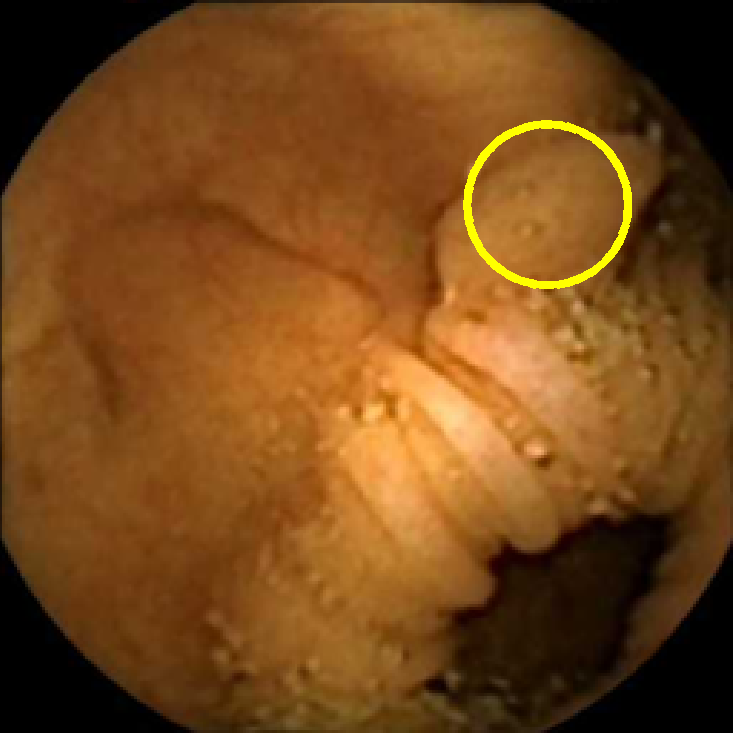

We illustrate the above considerations in Figure 4, where we compare the ellipses of inertia for a polyp frame and two frames with pronounced mucosal folds. The ellipses we plot are

| (20) |

where . The scaling term in front of is chosen so that the area of the ellipse of inertia is the same as the size of the corresponding feature.

As expected, we observe that the ellipses corresponding to mucosal folds (feature 2 in the second row and features 2 and 3 in the third row of Figure 4) are indeed much more stretched out than the ellipse corresponding to a polyp (feature 1 in the first row of Figure 4). Stretched ellipses imply higher eccentricity, thus we impose the following criterion

| (21) |

with some threshold to select moderately stretched features that are more likely to correspond to polyps.